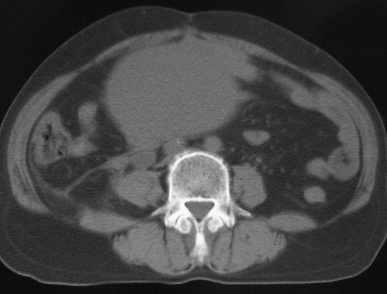

女56岁以右输尿管结石入院

病灶位于下腹部盆腔,从子宫与膀胱明显受压后移看,应该来源于盆腹腔的占位,病灶实性部分密度均匀,左侧可见低密度灶,建议增强扫描,考虑:间叶性肿瘤,或硬纤维瘤,输尿管下段结石伴上段输尿管扩张

右侧盆腔占位,考虑来源于卵巢,囊腺瘤可能性大。

右侧输尿管结石。

1)盆腔占位性病变,考虑来源于卵巢,囊腺瘤可能性大。2)右侧输尿管第二狭窄处结石伴梗阻。

今天病人已经手术证实为右附件囊肿,右侧输尿管第二狭窄处结石伴梗阻!!!

[病理诊断] CT11527:右附件囊肿,右侧输尿管结石。